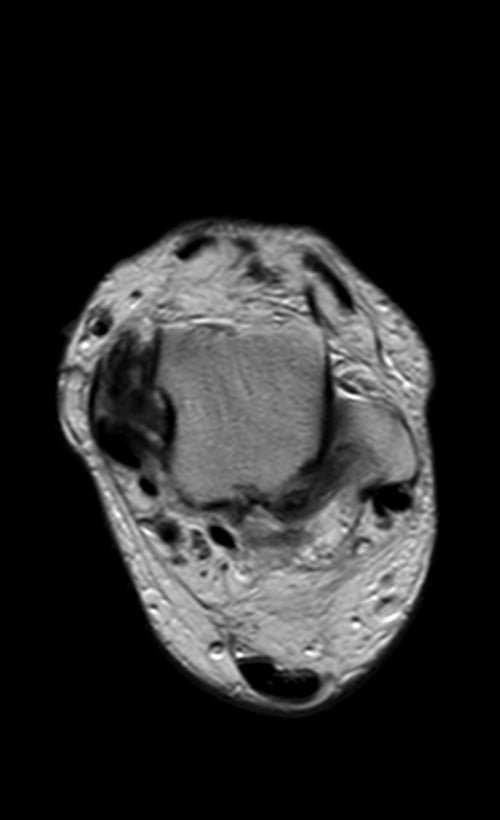

MRI ANKLE AXIAL PD IMAGE 3 - MRI